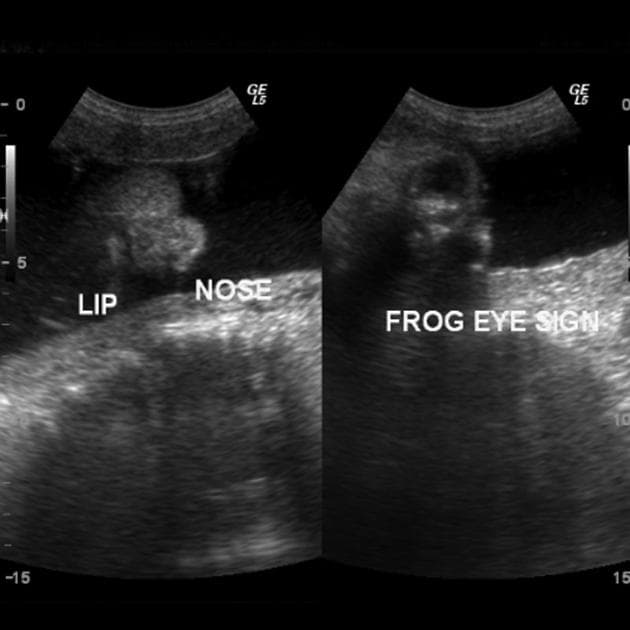

- Hình ảnh 3D của bại liệt tủy sống (3D image of spina bifida)

Siêu âm cho thấy sọ dạng quả chanh (lemon-shaped skull), dấu hiệu chuối (banana sign) ở tiểu não và mất hình ảnh thanh ray của cột sống. Chẩn đoán bại liệt tủy sống mở (open spina bifida) được xác định, hỗ trợ bởi siêu âm 3D và nồng độ alpha-fetoprotein (AFP) huyết thanh mẹ tăng cao. Nồng độ AFP là 320 ng/ml, vượt quá ngưỡng tham chiếu theo tuổi thai (ngưỡng tham chiếu: 10–150 ng/ml). Tiếc rằng thai phụ chuyển dạ tự phát lúc 22 tuần thai và trẻ sơ sinh tử vong trong vòng vài phút sau sinh. Thai nhi có khuyết tật ở cột sống thắt lưng, chỉ được che phủ bởi một màng mỏng.

Dấu hiệu chanh (Lemon sign) được biểu hiện bằng sự lõm vào của xương trán, tạo hình dạng giống quả chanh. Dấu hiệu này thường liên quan đến dị tật Chiari II và xuất hiện ở 90–98% trường hợp thai nhi bị bại liệt tủy sống. Khi đánh giá dấu hiệu này, cần tránh nghiêng đầu dò về phía trước (anterior angulation) vì hốc mắt có thể tạo hình ảnh giả giống dấu hiệu chanh 3.

Tiểu não bình thường ở thai nhi có hình dạng giống quả tạ (dumbbell-shaped), gồm hai bán cầu bên và thùy giun tương đối nhỏ. Sự sa xuống của các cấu trúc hố sau và tình trạng dính tủy sống dẫn đến mất khoang tiểu não (cistern magna). Hậu quả là tiểu não không phát triển hoặc có dạng cong bất thường về phía trước, tạo nên hình ảnh “dấu hiệu chuối” (banana sign) 4.

- "Dấu hiệu 'chanh' (lõm xương trán) xuất hiện ở 90–98% trường hợp thai nhi bị nứt đốt sống mở và là dấu hiệu siêu âm sớm gợi ý bệnh lý."

- "Dấu hiệu 'chuối' xảy ra do sa tiểu não do dị tật Chiari II, dẫn đến mất khoang tiểu não."